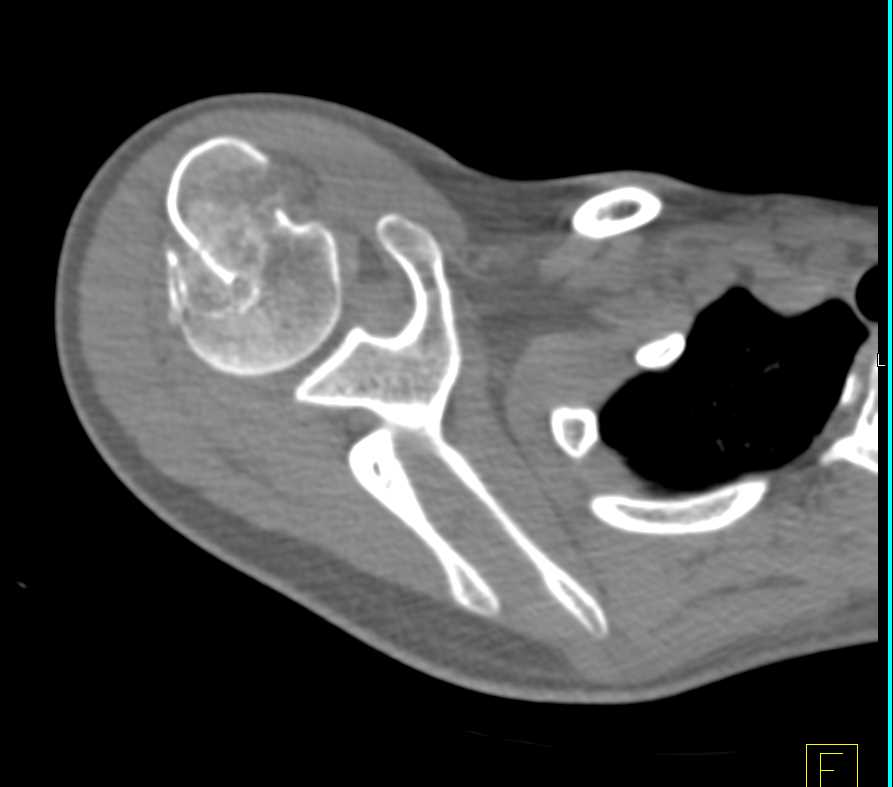

GSW with Bleed Near Knee